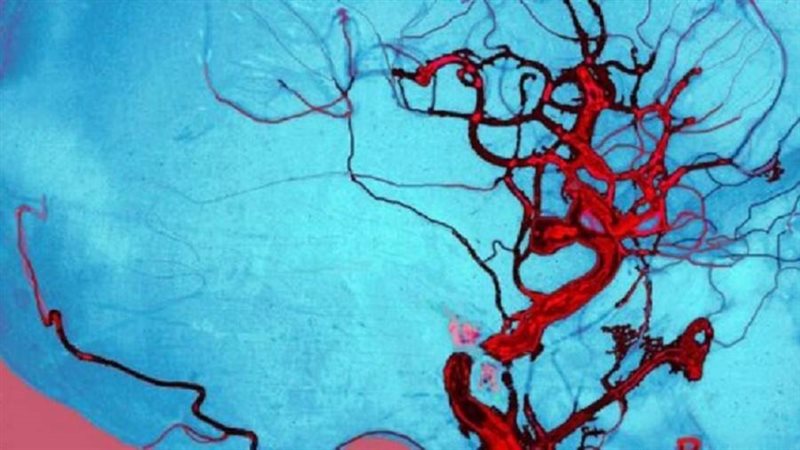

وفي الدراسة، حلل الباحثون النظام الغذائي وصحة 684 امرأة مسنة. وكشف التحليل أن النساء اللائي تناولن أكثر من 45 غراما من كرنب بروكسل أو الكرنب أو البروكلي يوميا، كن أقل عرضة للإصابة بأمراض الأوعية الدموية بنسبة 46٪، مقارنة بالنساء اللائي لم يأكلن خضروات. وأوضحت الدكتورة لورين بليكينورست، التي قادت الدراسة: "في دراساتنا السابقة، حددنا أن الأشخاص الذين يتناولون كميات أكبر من هذه الخضروات لديهم مخاطر أقل للإصابة بأمراض القلب والأوعية الدموية، مثل النوبة القلبية أو السكتة الدماغية، لكننا لم نتأكد من السبب. وتوفر النتائج التي توصلنا إليها من هذه الدراسة الجديدة نظرة ثاقبة للآليات المحتملة المعنية". وأضافت: "وجدنا الآن أن النساء المسنات اللائي يستهلكن كميات أكبر من الخضراوات هذه كل يوم، لديهن احتمالات أقل لظهور تكلس كبير في الشريان الأبهر. وأحد المكونات المحددة الموجودة بكثرة في هذه الخضروات، هو فيتامين K الذي قد يكون له دور في تثبيط عملية التكلس التي تحدث في أوعيتنا الدموية". ويمكن أن تقلل أمراض الأوعية الدموية من تدفق الدم في جميع أنحاء الجسم، بسبب تراكم ترسبات الكالسيوم الدهنية على الجدران الداخلية للأوعية الدموية. وما يثير القلق أنه بمرور الوقت يمكن أن يزيد ذلك من خطر الإصابة بنوبة قلبية أو سكتة دماغية. وبينما تشير النتائج إلى أن تناول كرنب بروكسل أو البروكلي أو الملفوف يمكن أن يقلل من خطر الإصابة بأمراض الأوعية الدموية، هذا لا يعني أن هذه هي الخضروات الوحيدة التي ينبغي عليك تناولها. وخلصت الدكتور بليكنهورست، بالقول: "يجب أن نتناول مجموعة متنوعة من الخضروات كل يوم من أجل الصحة والعافية بشكل عام".